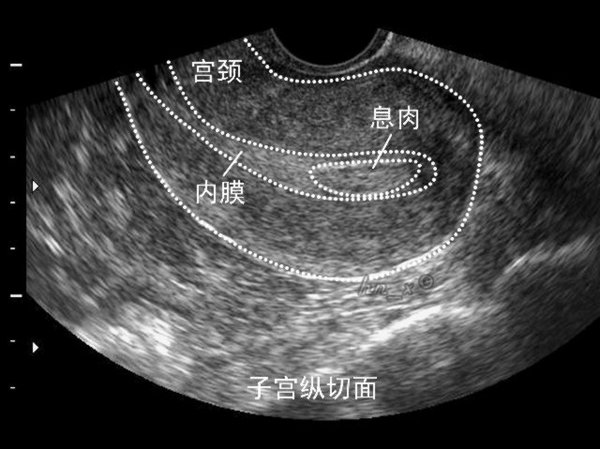

1、子宫内膜息肉是一种常见的妇科疾病, 是子宫局部内膜过度生长的结果,可谓是宫腔里的不速之客。无症状女性常在体检(或因其他疾病如不孕,月经不规律做检查)时意外发现子宫内膜息肉。年龄增长与激素补充治疗是其高发主要原因。子宫内膜息肉有复发的倾向(2.5%-3.7%)。子宫内膜息肉不仅仅只有手术治疗,如果息肉较小,直径<1层面,且无症状,可以观察随诊。一年内自然消失吕伟率为27%。你刚做过手术,我不建议短期内再次手术,可以观察一段时间。

对你来说,子宫内膜息肉也可以影响月经,导致月经间期出血,月经过多,或不规则出血,甚至不孕。你已做息肉手术,建议先观察一段时间。另外,还应排除精神因素造成的月经不调。你正在做生育准备,往往会过度关注月经,精神压力过大,也可引起月经的一些变化。

子宫是孕育胎儿的暖房。在这一亩二分地上,任何不速之客都是不受欢迎的。对于患有息肉的不孕妇女,手术切除息肉有助于增加受孕的几率。据研究报道,进行试管婴儿的不孕妇女,子宫内膜息肉患病率为32%。也就是说,子宫内膜息肉与不孕有着密切联系。你已经做过两次手术,再次手术需要慎重。观察一段时间也是必要的,因为小的息肉可以自然消失。

我个人意见认为,在做试管婴儿的过程中,有许多影响成功率的因素是未知的,对于显而易见的不利因素(子宫内膜息肉)放任不管是不应该的。